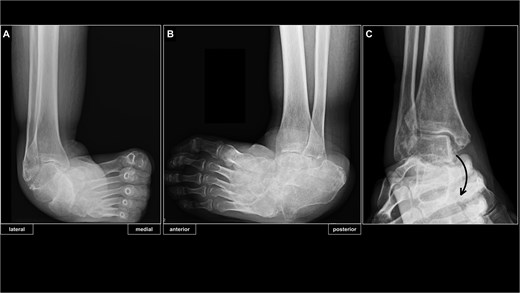

Preoperative radiographs demonstrated marked varus deformity of the ankle and abnormal weight-bearing on the lateral border of the foot (Fig. 2A and B). Under valgus stress, correction of the ankle and subtalar deformities was possible, but the midfoot inversion remained uncorrectable (Fig. 2C). Computed tomography revealed midfoot inversion associated with talonavicular subluxation (Fig. 3A and B). Based on these findings, surgical treatment aimed at achieving a plantigrade foot and restoring ambulation was planned.

Preoperative radiographs of the right ankle. (A) Radiograph of right ankle in the antero-posterior weight-bearing view. (B) Radiograph of right ankle in the latero-medial weight-bearing view. (C) Preoperative ankle stressed imaging showed correctability of ankle and subtalar joint deformities, but non-correctable subluxation of the talonavicular joint.